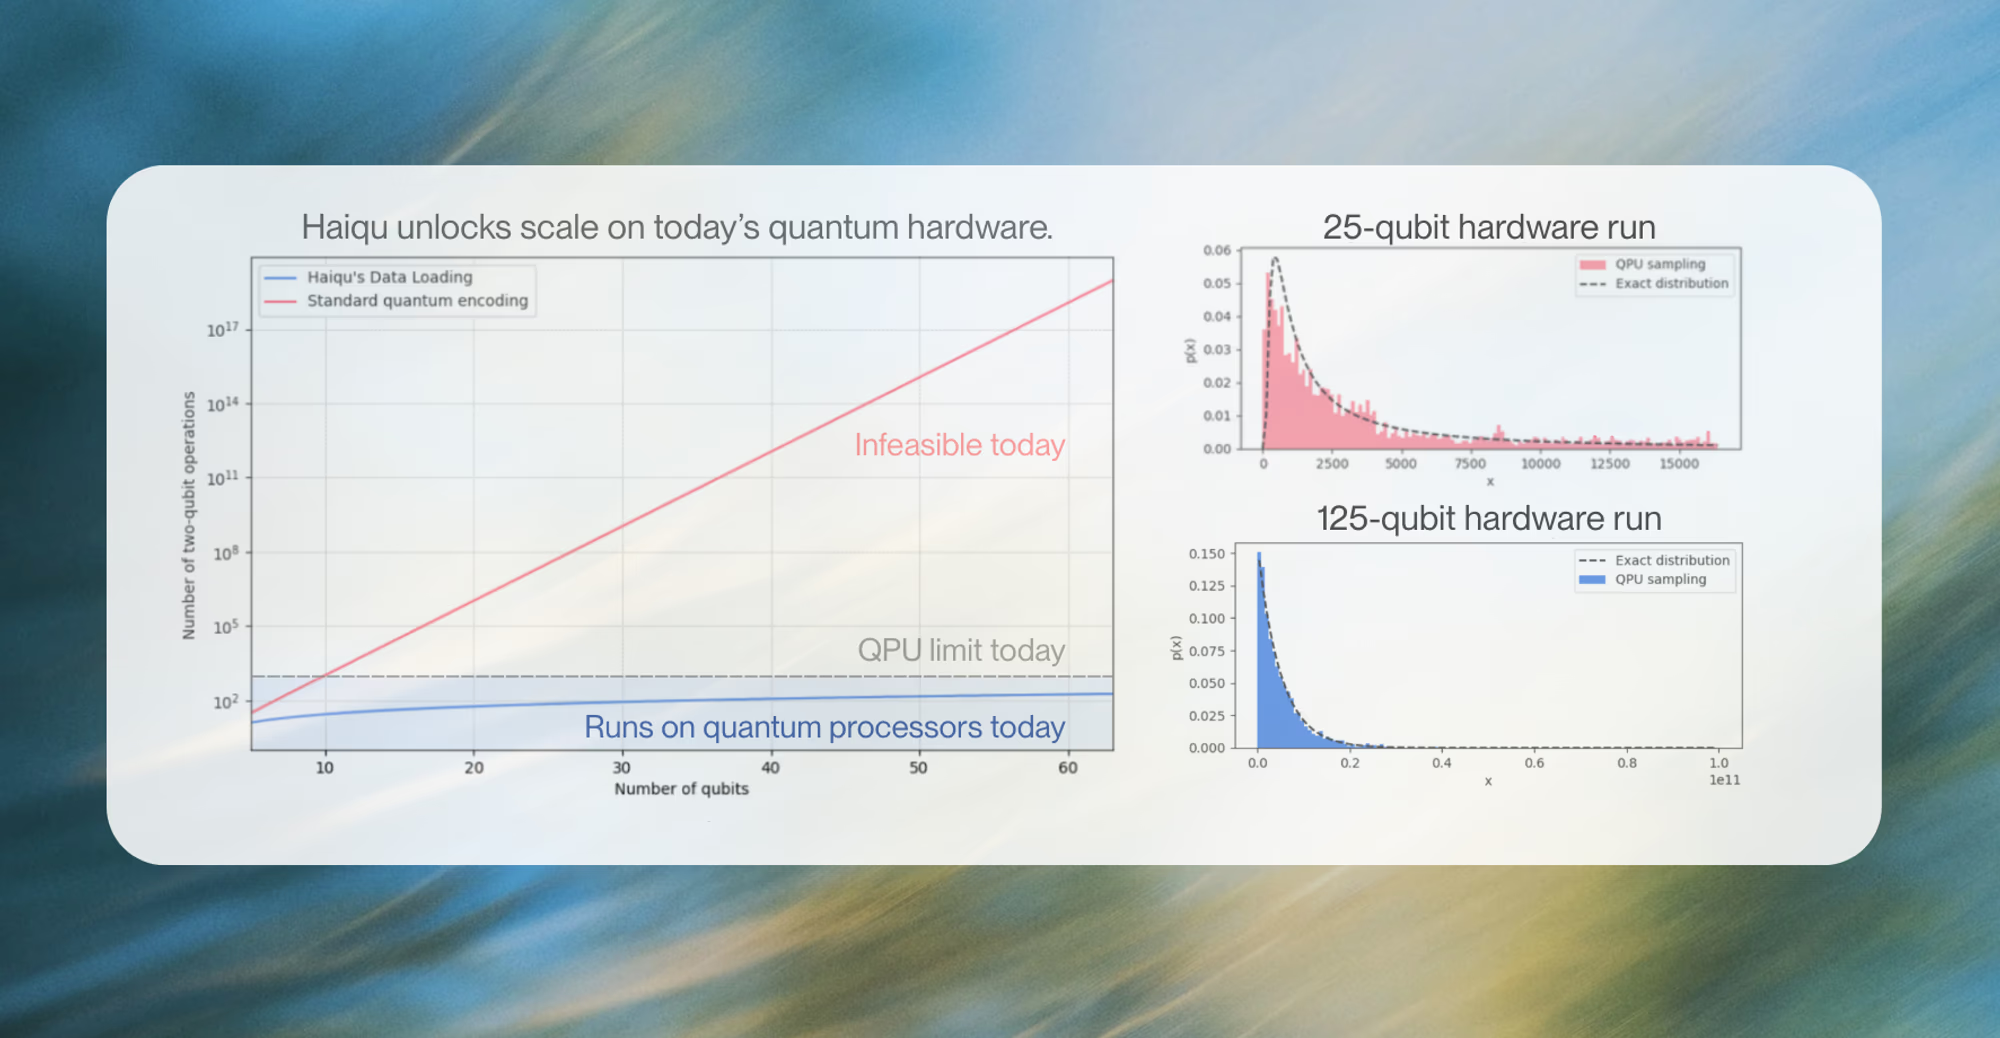

Problem: Quantum chemistry workloads exceed today’s hardware limits in circuit depth, noise, and cost.

Quantum computing offers a solution, but until now has been constrained by hardware noise, limiting usable circuit depth to a few hundred two-qubit gates. Haiqu, working with Capgemini, IBM, and GSK, broke this barrier by demonstrating one of the largest electronic-structure Hamiltonian simulations ever run on real quantum hardware for covalent drug warheads. Using advanced circuit compression and middleware execution, the team initially reduced circuit depth by 15.5× and further allowed end-to-end execution by running sub-circuits up to 371 gates.

Solution: Decomposed prohibitive quantum runs into hardware-friendly, separable blocks.

Collectively, these results establish a scalable, hardware-realistic path for running Hamiltonian simulations on larger active spaces, while maintaining sufficient accuracy for molecular reactivity prediction.